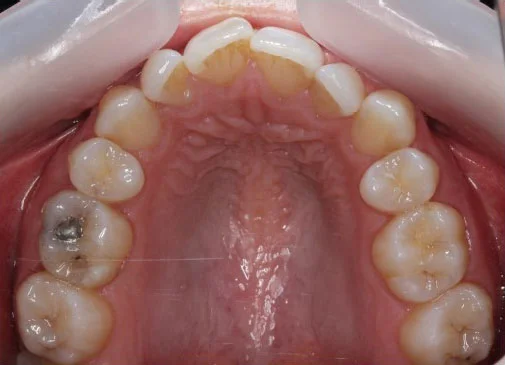

Our amazing Invisalign results

If you’re wondering whether Invisalign can really make a difference, simply take a look at these images below.

Case 5:

![]()